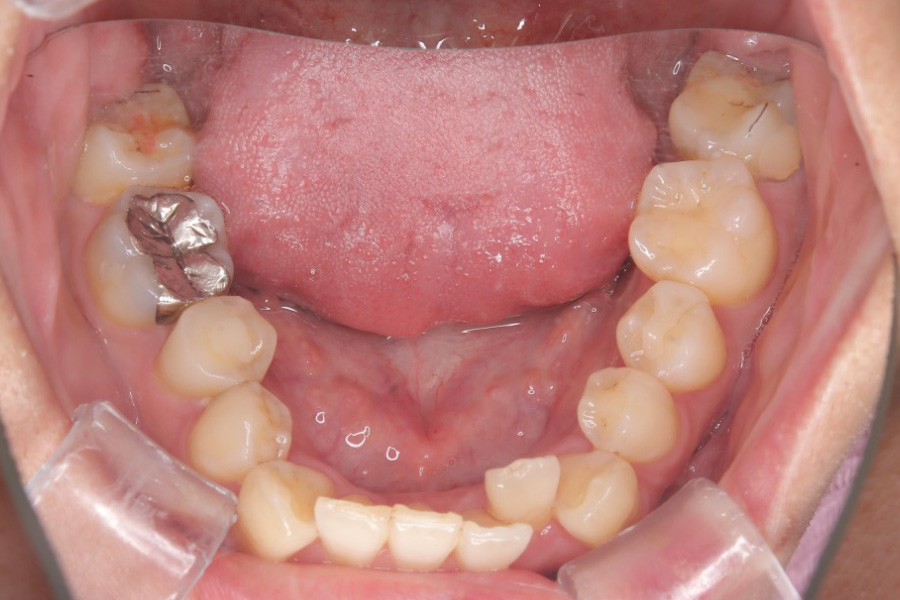

治療後

主訴 歯全体のガタつきが気になる

治療内容 インビザライン矯正

小臼歯抜歯